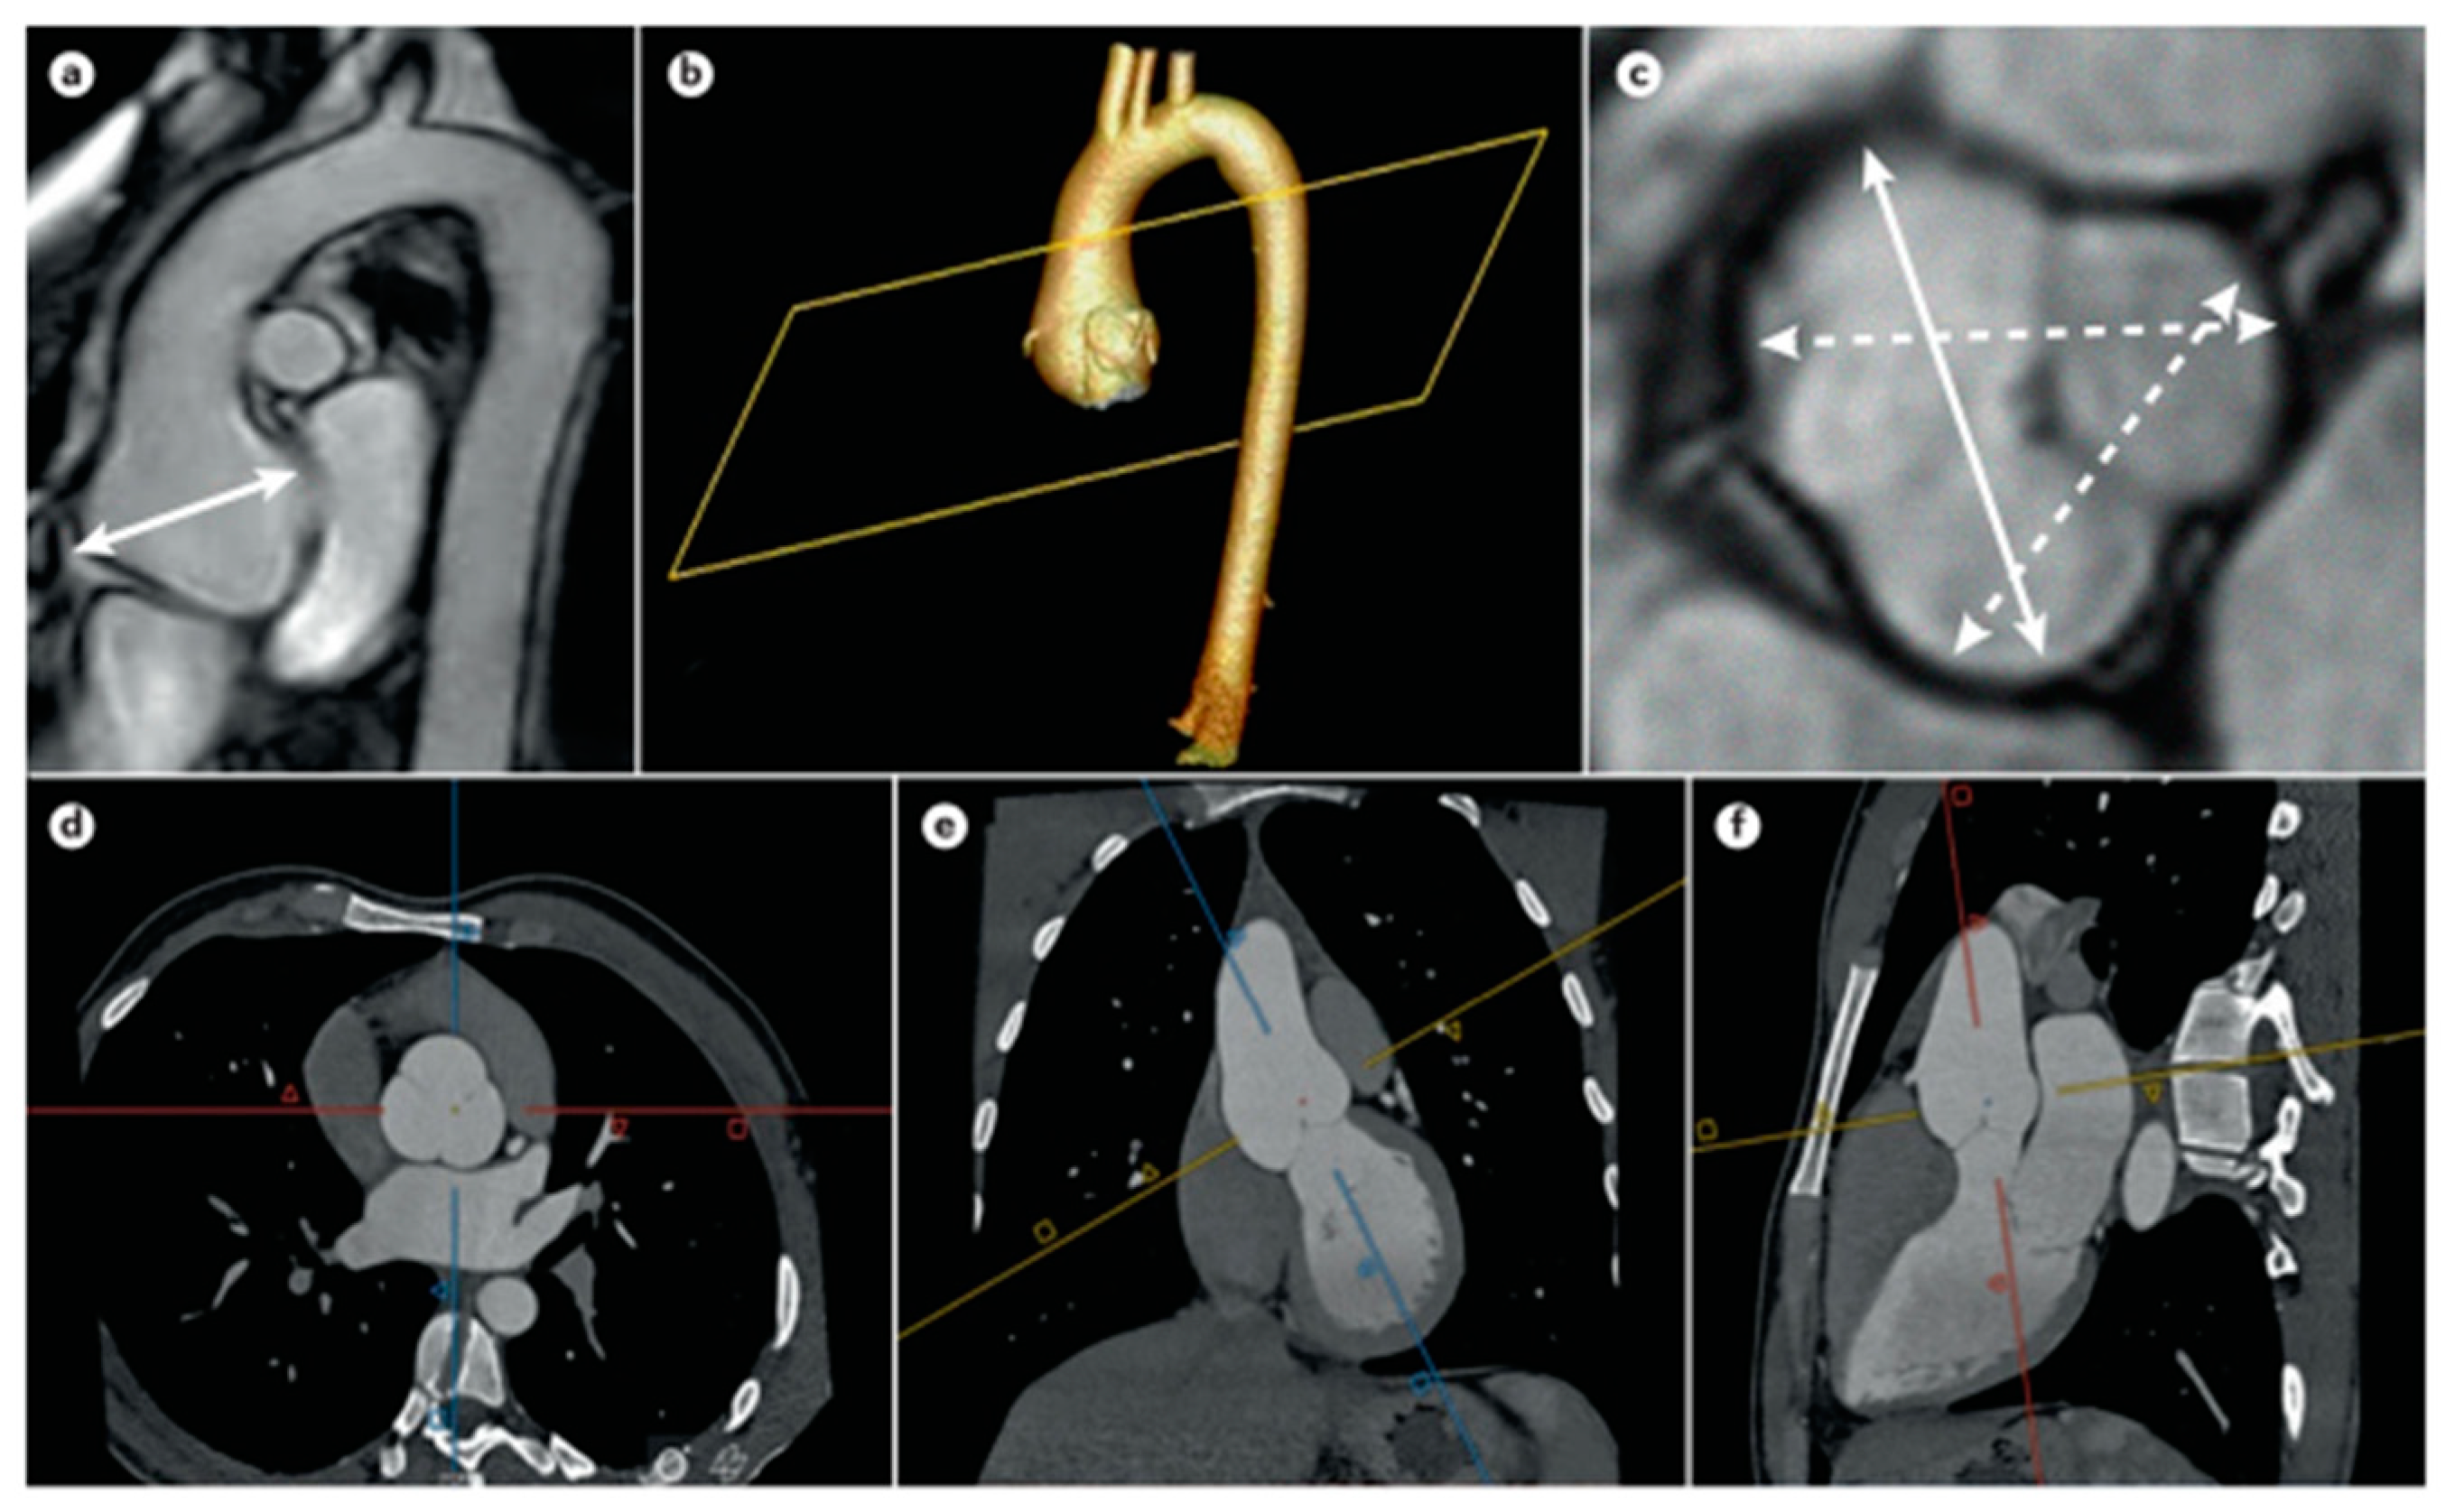

Therefore, any patient, whether a child or adult, being evaluated for MFS should undergo an echocardiogram (Figure 8) [37]. However, at the time of diagnosis, in addition to TTE, a global evaluation of the aorta (arc, descending aorta, and abdominal aorta by CT or MRI) is useful.

Figure 8.

Aortic aneurysm in MFS. (a,c) Aortic root aneurysm by MRI measured in sagittal projection and transversal projection, evaluating cusp to cusp diameters at end-diastole; (b) 3D reconstruction of CTA imaging (d–f) of an aortic root aneurysm; the double acquisition of sagittal and coronal images allows for a more correct transversal diameter of the aortic lumen. Adapted with permission from [37].

Furthermore, since the growth rate of the aorta in patients with MFS is higher than in others, continuous instrumental evaluation (echo, CT, and MRI) is essential over time [38,39]. If the diameter of the aorta remains stable below 45 mm, annual checks can be performed; if the aorta is larger than 45 mm, more frequent checks are recommended [40]. If TTE is not technically feasible (e.g., due to chest malformations), an MRI evaluation is recommended to reduce the radiation rate and ensure greater protection of the kidneys.